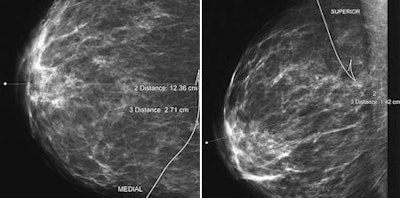

| The following images are of a 46-year-old woman with one-view asymmetry in right breast. Above, craniocaudal projection mammogram of both breasts shows one-view asymmetry (arrow) in medial aspect of right breast. All images courtesy of the American Roentgen Ray Society. |